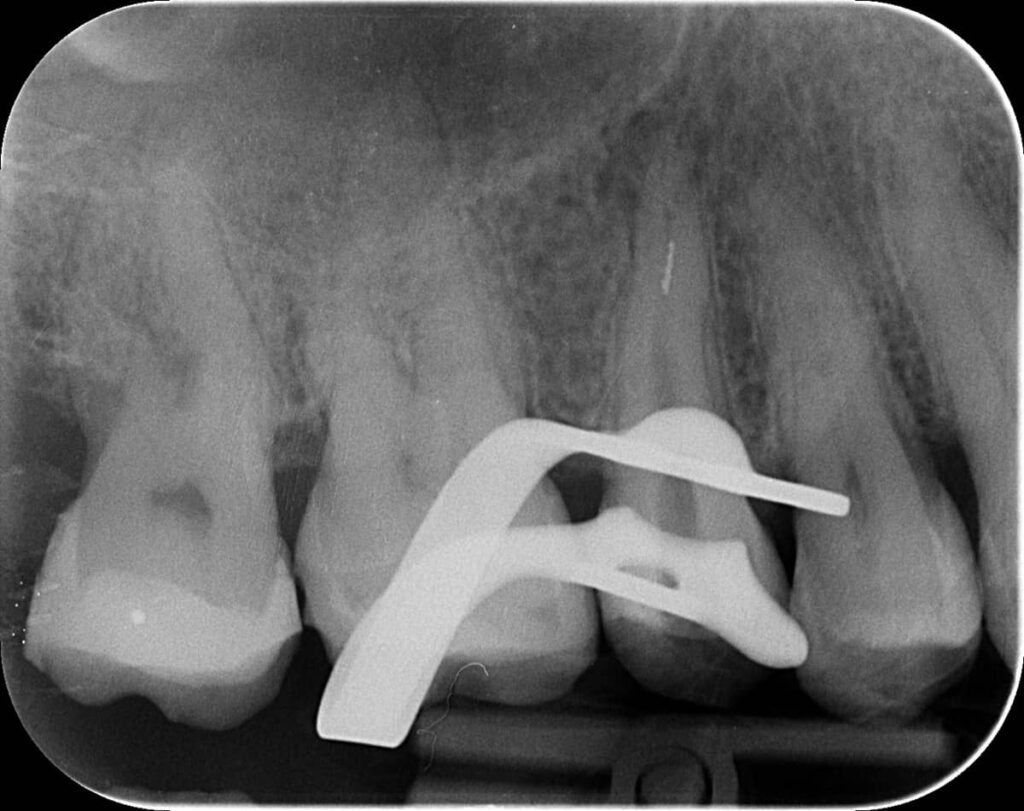

Az érintett jobb felső ötös fogról a páciens már egy kis fogfelvétellel érkezett. A kezelés megkezdése előtt a röntgen megtekintésekor feltűnt, hogy valószínűleg nem egy, hanem két betört fragmentumról van szó. Ezek a fogak gyakran két csatornával rendelkeznek, illetve ebben az esetben egy érdekes variációval: a két csatornának közös vége van. Ilyenkor az egymás felé ívelő gyökércsatornák meglehetősen görbék lehetnek - tipikus helyei a tűtöréseknek.

mikroszkópos gyökérkezeléssel megmentett fog: a bent rekedt fragmentumok eltávolítása 1

Először a szájpadlás felőli gyökércsatornában tártuk fel a tűt. Óvatosan, a megfelelő technikát alkalmazva sikerült eltávolítani a kb. 4 mm-es darabot. Ilyenkor készítünk egy kontrollröntgent, hogy lássuk, valóban nem maradt bent semmi az eltávolított tűből. Ekkor vált biztossá a gyanúnk, van még egy műszer a fogban.

mikroszkópos gyökérkezeléssel megmentett fog: a bent rekedt fragmentumok eltávolítása 2